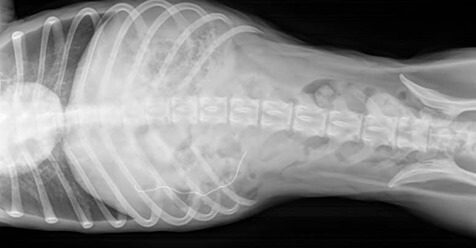

According to Channel 7News, the Animal Rescue League of Boston is caring for the dog now dubbed Gibbs. Upon diagnosis accompanied by an X-ray, nose wires from two discarded paper masks were visible. He is reported to be recovering well and is scheduled to be made available for adoption once he gains weight.